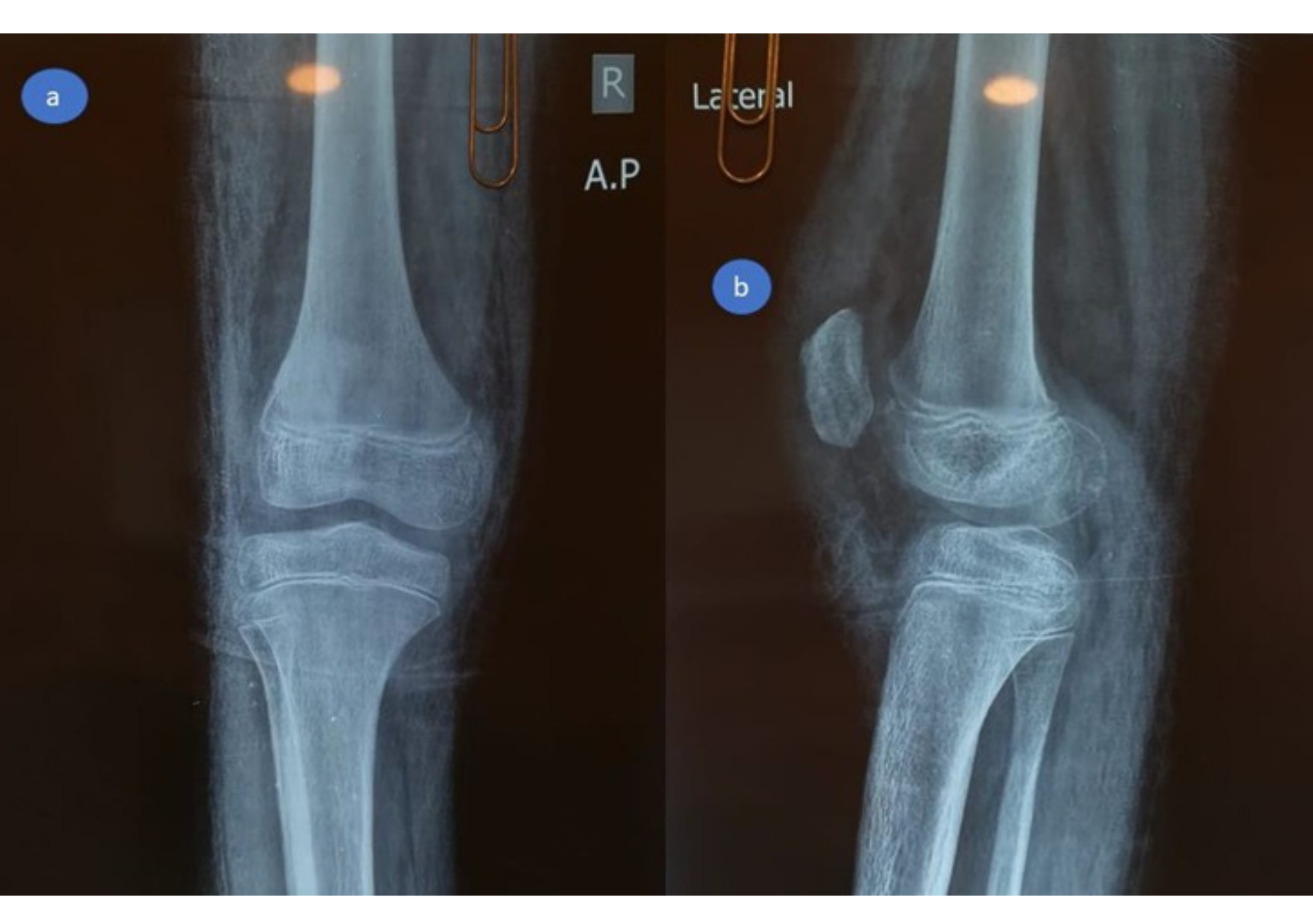

At the emergency room, radiographs were performed, which revealed a high-riding patella with a noticeable joint effusion as well as a small osteochondral fragment positioned distally to the patella. (Figure 2) As a result of the high-riding patella on the radiographs and the avulsion of the distal osteochondral side of the patella, a patellar sleeve fracture was detected. The surgery was scheduled for the next day.